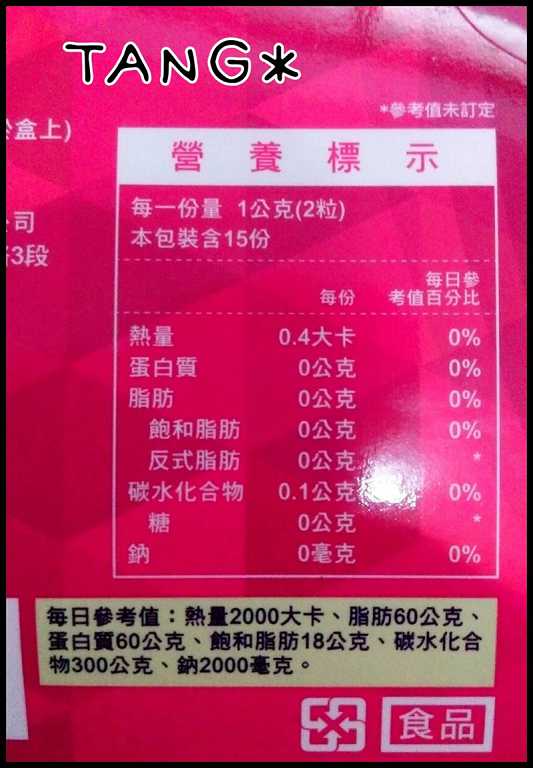

Supercut塑魔纖立塑膠囊的成分有:瓜拿那萃取粉、肉桂萃取粉、辣椒萃取物(唐辛子)、吡啶甲酸鉻、番瀉葉粉末、玉米澱粉、氧化鎂、二氧化矽。